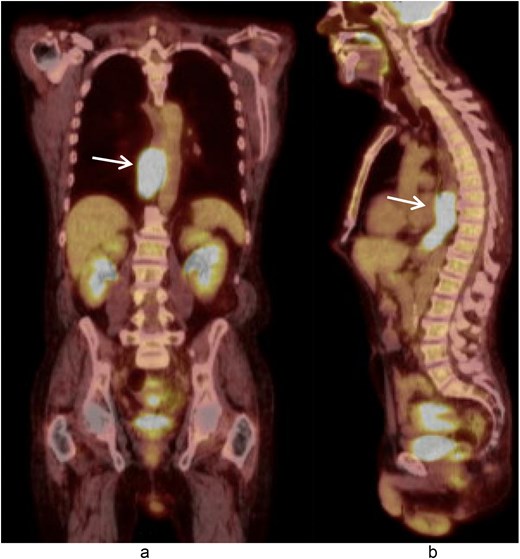

A multidisciplinary discussion was held and in the setting of the rapid tumor progression with biology favoring sarcoma and no evidence of distant disease, the decision was made to pursue upfront surgical resection rather than neoadjuvant therapy. The patient underwent a three field near total esophagectomy with an uneventful postoperative hospital course. A fluoroscopic esophagram was performed on postoperative day 6 without evidence of contrast extravasation (Fig. 4). The final pathology revealed an 8.7 cm high-grade pleomorphic rhabdomyosarcoma with mucosal and submucosal invasion, sparing the muscularis propria with 0/11 lymph node involvement (Fig. 5). This was formally graded as Stage IIIA (pT2N0M0), based on the soft tissue sarcoma criteria of AJCC.

Fluoroscopic esophagram showing an intact anastomosis without contrast extravasation on postoperative day 6 status post-esophagectomy.